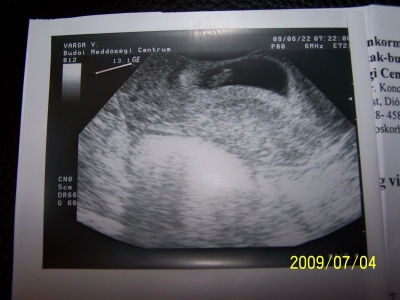

Lefényképeztem végre a legutóbbi uh-mat. Itt már 8mm-es a babó. Remélem kedden hozhatom a frisset. Tegnap meg volt életem első terhes hányása. Alig értem be a mamut wc-jébe. De utána már nem volt semmi bajom. Megnéztük a Jégkorszak 3-mat és utána megvettem életem első kismamás cuccát. Bementünk bandázst nézni a bababltba, de az valahogy nem volt az igazi, de vettem magamnak egy olyan fürdőruhát, amilyet szerettem volna. Tankinis fekete és van rajta hímzés. Tegnap megpróbáltam ezt is lefotózni, de nagyon sötét volt már. Ez volt az utolsó darab belőle. Párom szerint nagyon jól áll (na ja, kivan belőle a fél csöcsöm :) ). Szóval ezek voltak tegnap.

Szóval a babó: